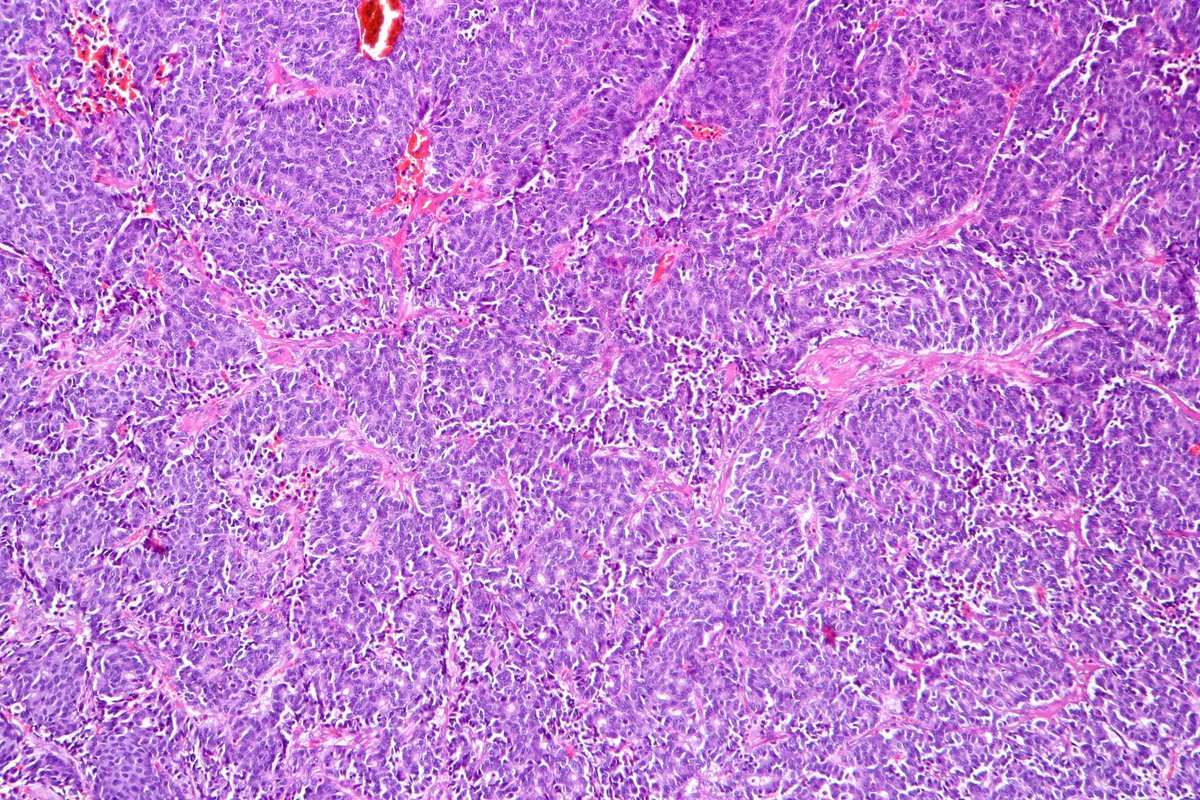

Type B2 Thymoma showing prominent large epithelial cells admixed with numerous lymphocytes. #pathology #PulmPath